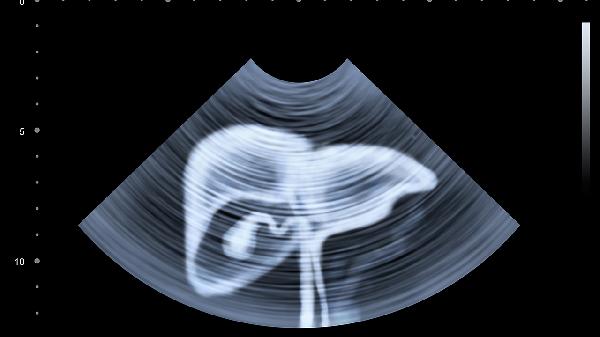

腹部烧热感可能由胃食管反流、慢性胃炎、消化性溃疡、功能性消化不良、胰腺炎等原因引起,可通过调整饮食、药物治疗、内镜治疗、生活方式干预、手术治疗等方式缓解。腹部烧热感是一种常见的消化道症状,表现为上腹部或胸骨后的灼烧样不适。